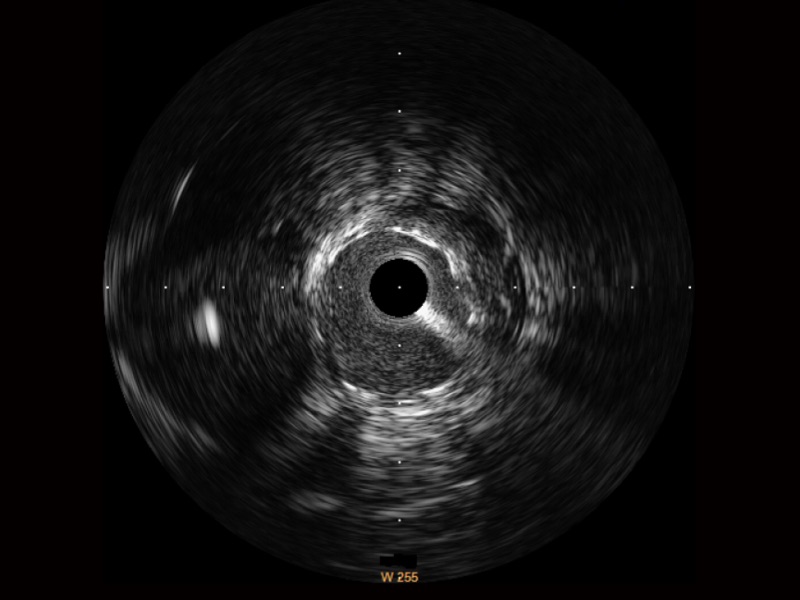

開立超寬頻成像技術(shù)覆蓋20-80MHz1或20-90MHz2頻率范圍, 提供優(yōu)異的分辨力同時也保證充足的穿透深度

對比傳統(tǒng)IVUS導(dǎo)管成像,開立寬頻IVUS圖像的近場支架梁顯影更細(xì)膩,遠(yuǎn)場中膜外血管仍清晰可辨,兼顧遠(yuǎn)中近,兼顧分辨力與穿透深度